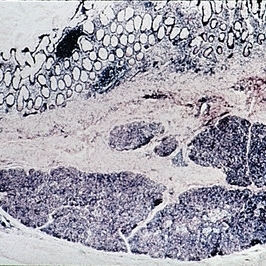

Dermoid cyst. The wall is lined by stratified squamous epithelium and contains epidermal appendages. The lumen, at top, contains keratin debris toward the left side (H&E x54).

Condition/keywords: cyst, lumen, stratified squamous epithelium